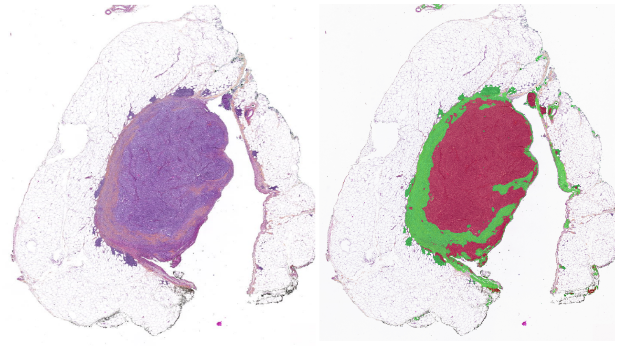

The primary mission of the PINKCC Lab is to transform the understanding and analysis of tumor habitats and phenotypes. By integrating advanced multi-omics approaches with extensive clinical in vivo imaging data, we aim to build a comprehensive depiction of cancer. A major innovation is the development of virtual cancer biopsies, designed to use MRI to decode complex histological and molecular characteristics traditionally obtained through invasive procedures.

Virtual Biopsies Example

Two main projects support this vision: MROMICS (ERC-funded), focusing on virtual biopsies for high-grade serous ovarian cancer, and PANCOMICS (ARC Foundation-funded), applying the approach to pancreatic cancer.

Both ovarian and pancreatic cancers share a major challenge: an extremely poor prognosis, driven by late diagnosis and limited understanding of biological heterogeneity. Conventional biopsies sample only a small fraction of the tumor, whereas non-invasive imaging combined with radiomics offers a powerful alternative. Our goal is to correlate high-field preclinical MRI (9.4T) information with spatial transcriptomics to extend findings to clinical MRI and predict the tumor’s molecular and genetic status.

We also develop non-invasive biophysical MRI characterization techniques—hypoxia, pH, acidity, elasticity—combined with AI to build predictive models for virtual cancer modelling.